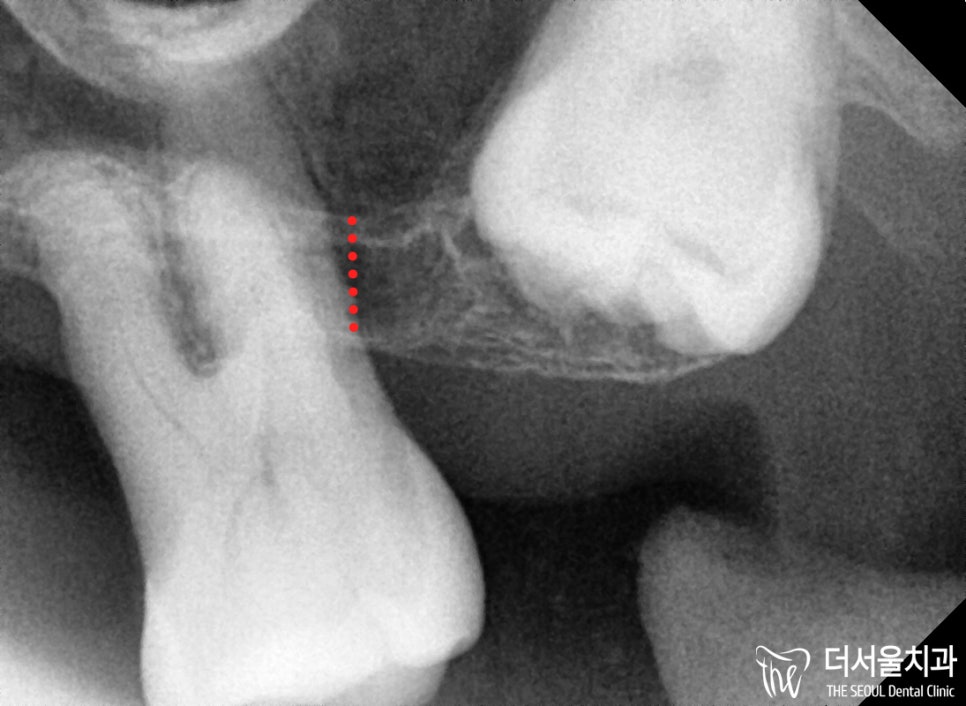

우선 잇몸뼈가 얼마나 남아있는지

정확한 진단이 필요했기에

파노라마 엑스레이를 촬영하여 확인해봤는데요.

2. 뼈 상태 체크

치아가 있는 곳을 제외하고는

잇몸뼈는 거의 없는 상태입니다.

특히 윗부분은 상악동의 막과

거의 손톱만큼의 거리가 될 정도로

정말 얇은 것을 볼 수 있죠.

끝에 있는 어금니는

뿌리만 살짝 걸치고 있을 정도로

남아있는 뼈가 없는 상태였습니다.

또, 이미 흔들림이 커서 발치를 해야 되었구요.

옆에 숨어있는 사랑니는

맹출되지 않았기에

굳이 건드리지 않기로 합니다.

그리고 앞니 역시 마찬가지로

뿌리 끝에만 걸치고 있는 상황이었습니다.

아래에 검사를 하는 부분에서

보여지는 것처럼

뼈 상태가 너무 좋지 않기에,

추가적으로 뼈이식을 하기로 합니다.

좀 더 확대해서 보면,

이렇게 픽스처가 골폭을 벗어나있죠?

이러면 제대로 고정되지 않습니다.

결국, 실패로 이어지기에

뼈이식을 해야 되었죠.

그리고 파노라마 엑스레이로

뼈이식과 임플란트 식립이 잘 되었는지,

마지막으로 한 번 더 체크해줍니다.